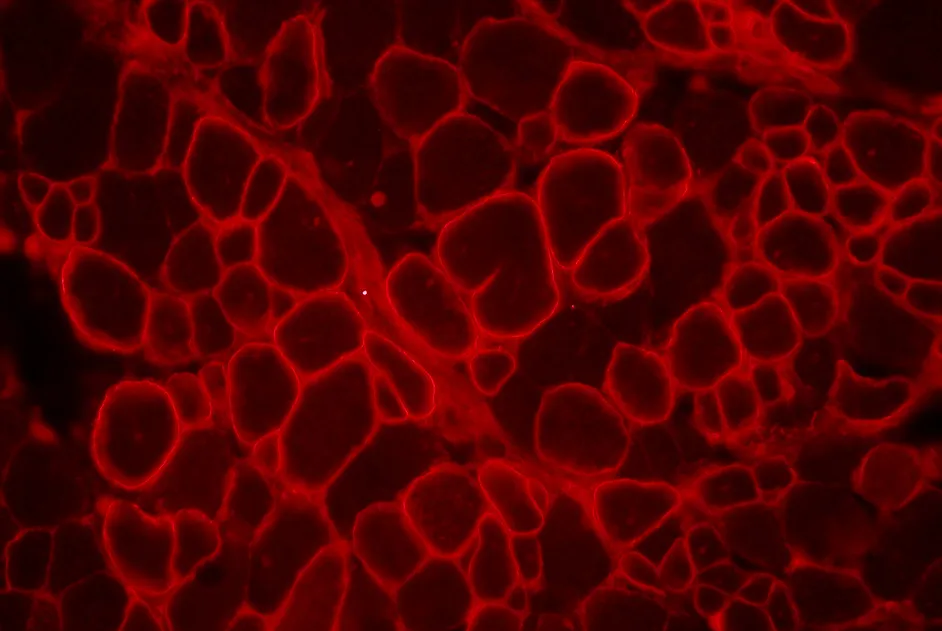

Les premiers malades sont guéris. Masi des milliers d’autres attendent une solution. Laurence Tiennot-Herment, présidente de l’AFM-Téléthon, explique pourquoi vos dons sont vitaux pour la recherche et l'aide aux malades.